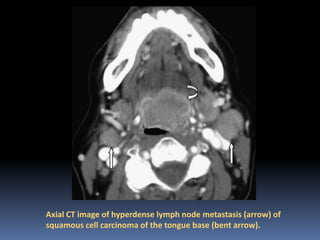

Axial CT image of hyperdense lymph node metastasis (arrow) of

squamous cell carcinoma of the tongue base (bent arrow).